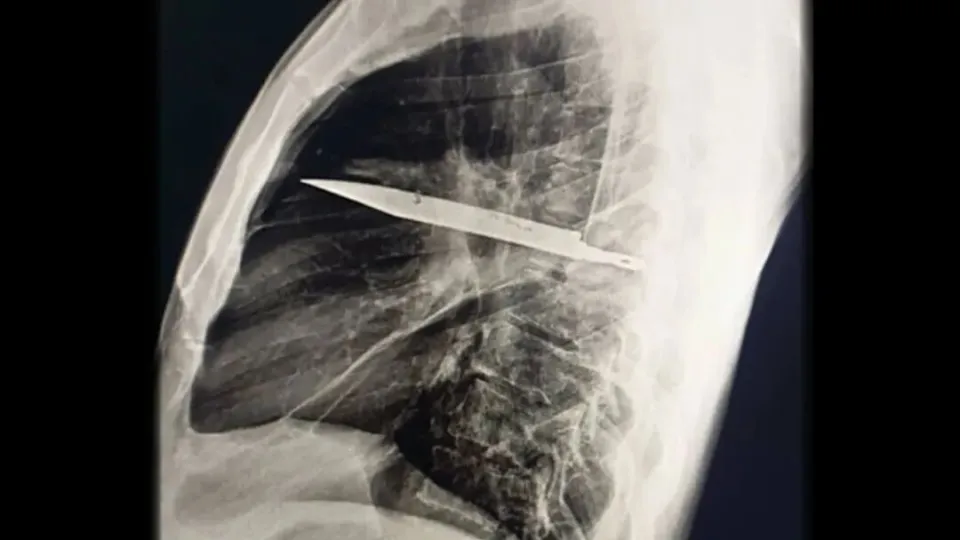

影像学检查给出了颠覆性答案:X 光片上,一把金属断刃如鬼魅般卡在胸腔中部,从背部第五、六肋骨间刺入,刀尖直抵前胸第三、四肋骨之间,仿佛一柄悬在心脏与肺叶间的利刃。更令人难以置信的是,CT 扫描显示,患者肩胛骨及多根肋骨的骨折早已愈合,而这把刀的 “潜伏” 时间,竟长达 8 年。

2025 年 5 月,坦桑尼亚医疗团队为患者实施了紧急开胸手术。当手术刀划开胸壁,包裹着断刀的纤维囊被逐层剥离,恶臭的脓液与坏死组织随之涌出 —— 这层曾经的 “保护罩”,在 8 年后已然沦为感染病灶。医生小心翼翼地取出断刀,用氯化钠溶液反复冲洗胸腔,放置引流管后缝合伤口。术后 7 天的广谱抗生素治疗与严密监护,终于让患者在术后 10 天顺利出院,两次复查均未发现感染或并发症。